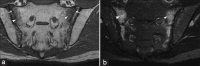

Musculoskeletal disorders are among the most common problems affecting the elderly. The resulting loss of mobility and physical independence can be particularly devastating in this population. The aim of this article is to present some of the most frequent musculoskeletal disorders of the elderly, such as fractures, osteoporosis, osteoarthritis, microcrystal disorders, infections, and tumors.

- Gotis-Graham I, McGuigan L, Diamond T, Portek I, Quinn R, Sturgess A, et al. Sacral insufficiency fractures in the elderly. J Bone Joint Surg Br. 1994;76:882–6. - PubMed